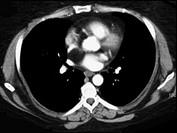

问题 女性,40岁,活动后心慌一年余,彩超发现左心房有异常回声,CT检查如图所示,应考虑为 ( )

选项 A、正常左心房 B、左心房脂肪瘤 C、左心房血栓 D、左心房脂肪浸润 E、左心房黏液瘤

答案 B